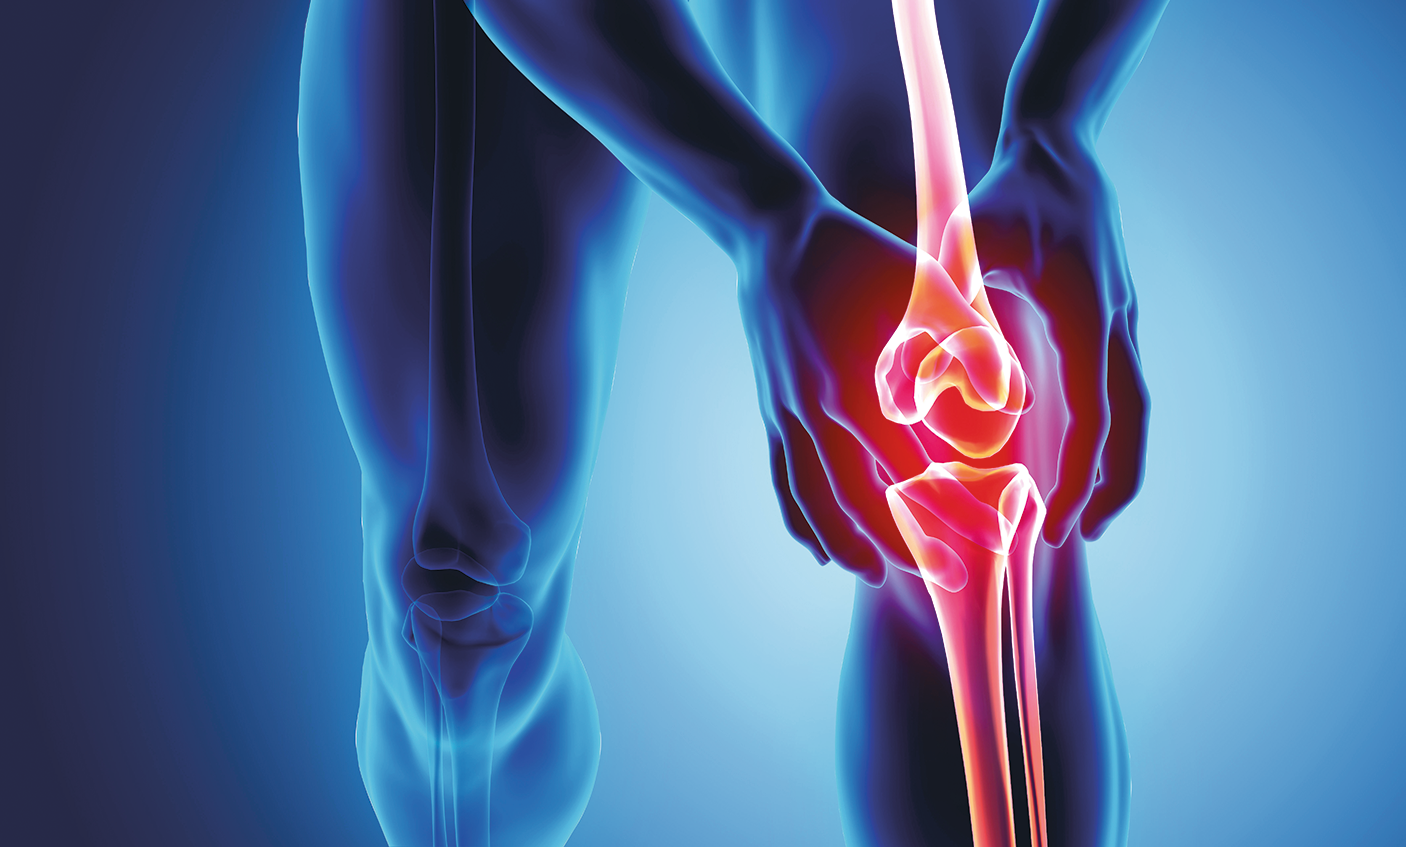

Медицинские состояния: Септический артрит коленного сустава